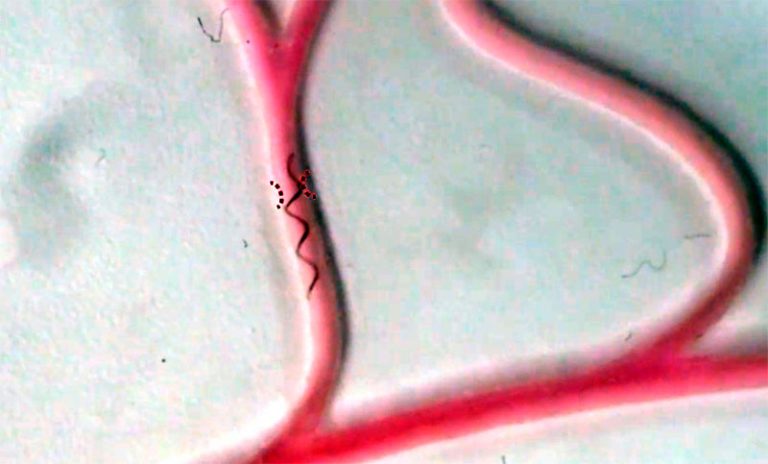

Asimismo, explicaron que, al «controlar los campos magnéticos, los robots exhiben una transformación reversible de formas alargadas/agregadas y una propulsión helicoidal en condiciones de flujo, lo que permite una navegación controlable a través de una vasculatura compleja» y la embolización (privar de irrigación sanguínea) a voluntad del objetivo elegido.

«El robot de microfibra, compuesto por una fibra magnetizada enrollada en forma de hélice, puede adaptarse a diferentes tamaños de vasos y realiza una propulsión en forma de sacacorchos cuando se lo somete a un campo magnético externo», escribió Melisa Yashinski, editora asociada de Science Robotics.

Los creadores realizaron pruebas de embolización ‘in vitro’ de aneurisma y tumor en fantasmas neurovasculares (modelos artificiales). También llevaron a cabo la embolización ‘in vivo’ de un modelo de arteria femoral de conejo bajo fluoroscopia en tiempo real. Los resultados fueron positivos.